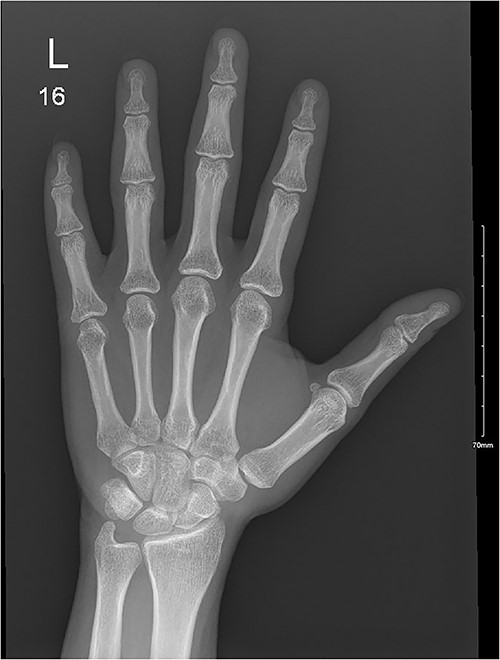

A 32-year-old male presented to the emergency department with a painful, discolored, and edematous left thumb following spontaneous deployment of his automobile’s airbag. On physical examination, the thumb’s range of motion (ROM) was reduced because of pain. Radiography showed a tuft fracture of the thumb’s distal phalanx (Fig. 1). The patient was managed conservatively with a Zimmer splint and followed-up 1 week later. Magnetic resonance imaging (MRI) was obtained to assess for the presence of ligamentous injury showed complete tearing and proximal retraction of the distal attachment of the ulnar collateral ligament in (Fig. 2), so the patient was given a thumb spica and was booked for surgery. In the operating room, the ulnar collateral ligament was identified and was indeed completely avulsed from its distal attachment site. The ligament was repaired using the Kessler tendon repair maneuver, ultimately ending with the thumb flexed 30° at the metacarpophalangeal (MCP) joint. This patient was followed-up for 103 days after his first presentation. On his final clinic visit, the thumb was stable, the wound was fully healed, and full ROM was regained.

A comminuted slightly displaced fracture of the tip of the left fifth distal phalanx.